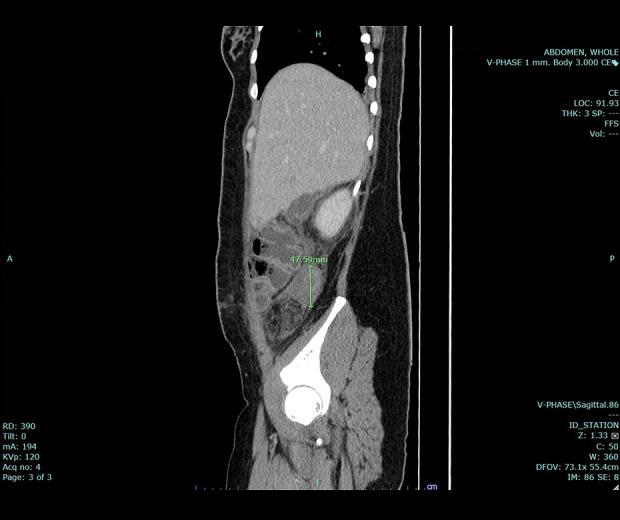

BACKGROUND Uterine dehiscence, an infrequent event often mistaken for uterine rupture, is rarely linked to post-cesarean section procedures and can result in severe complications, notably puerperal sepsis. In this report, we present a case that exemplifies the onset of puerperal sepsis and the emergence of intra-abdominal abscesses attributed to uterine dehiscence following a lower segment cesarean section (LSCS). CASE REPORT Our patient, a 28-year-old woman in her third pregnancy, underwent LSCS 1 week earlier. Subsequently, she returned to the hospital with lower abdominal pains, fever, and malodorous vaginal discharge. Computed tomography (CT) scan of whole abdomen verified uterine dehiscence and pus collection at the subhepatic region and right paracolic gutter. After referral to a specialized hospital, laboratory findings indicated an elevated white blood cell count and alkaline phosphatase levels, and coagulation abnormalities. She underwent an exploratory laparotomy, which unveiled uterine dehiscence, abscesses, and adhesions, necessitating a total abdominal hysterectomy and abdominal toileting. Pus culture analysis identified the presence of E. coli, which was susceptible to ampicillin/sulbactam. Complications were encountered after surgery, including wound dehiscence and pus re-accumulation. Successful management involved vacuum dressings and percutaneous drainage. Eventually, her condition improved and she was discharged, without additional complications. CONCLUSIONS This report underscores the importance of considering cesarean scar dehiscence as a diagnosis in women with previous cesarean deliveries who present during subsequent pregnancies with symptoms such as abdominal pain or abdominal sepsis. Diagnostic tools, such as CT, play pivotal roles, and the timely performance of an exploratory laparotomy is paramount when suspicion arises.